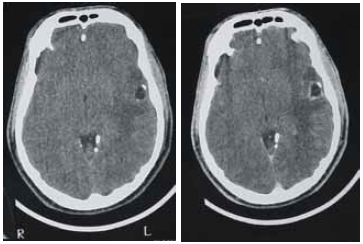

Uma paciente de 35 anos de idade foi levada ao prontosocorro após uma convulsão. Ao exame de admissão, encontravase confusa, sonolenta, porém reativa ao chamado. Apresentava sutil paresia braquiofacial direita. O esposo informou que, nos últimos cinco meses, a paciente começou a apresentar dificuldade para se comunicar, troca de palavras e dificuldade para nomeação. Há duas semanas, o quadro piorou e começou a ficar desligada e a apresentar abalos musculares no membro superior direito, de rápida duração, além de queixar-se de dor de cabeça. Foi realizada uma tomografia computadorizada (TC0 de crânio, sem e com contraste, obtendo-se as imagens a seguir.

A imagem mostra um edema vasogênico, que tem como base a ruptura da barreira hematencefálica, levando a aumento da permeabilidade e passagem de líquidos do espaço intravascular para o extravascular, extracelular.